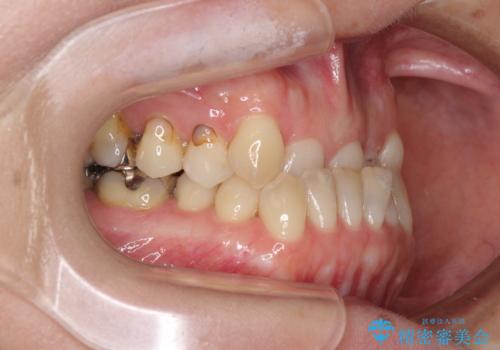

- 前歯の反対咬合を気にして来院された患者様です。

上顎骨の幅が下顎骨よりも小さいので、拡大装置により骨幅を広げて上下関係を改善すると同時にワイヤー矯正で反対咬合の改善を図り、その後インビザラインにて歯並びを整えることとしました。

上顎前歯の矮小歯は矯正治療の途中でオールセラミッククラウンを装着し、左右のバランスを整えることとしました。

急速拡大装置の使用により奥歯の咬み合わせが劇的に変わり、その変化を利用して反対咬合を改善することができました。

治療期間中は奥歯が咬み合わず、食事が取りにくいなどの不都合がありましたが、最終的にはきれいに整えることができました。